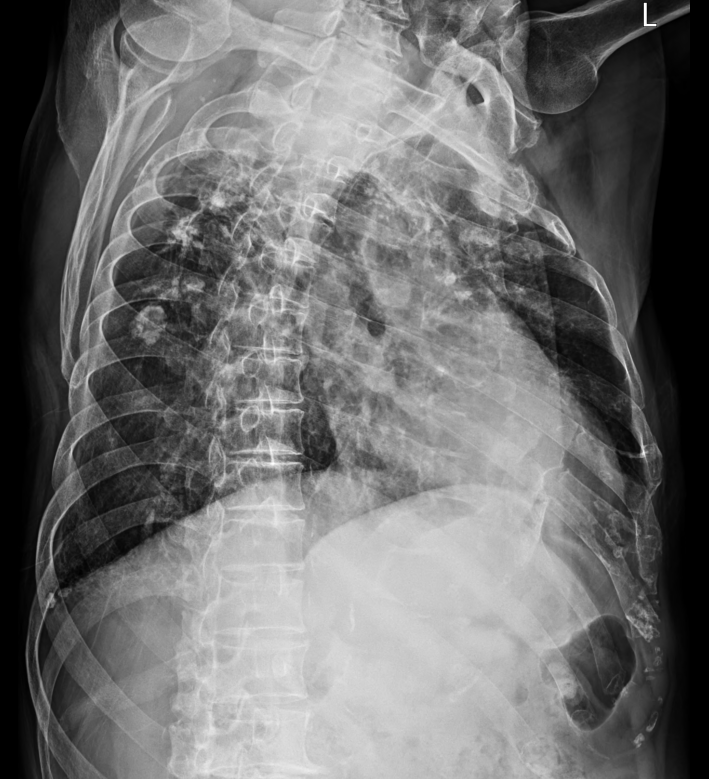

내원한 환자의 흉부 x ray 사진을 보던중..

x ray 만으로는 너무 애매(정보가 충분치 않다는 의미)하다는 생각을 하며

요즘 CT 기술의 발달과 접근성이 용이해지면서 x ray를 점점 소홀히 해가는 나를 보며.. 다시 기본으로 돌아가보자는 생각으로 x ray의 해석에 대해 공부해보고자 한다.